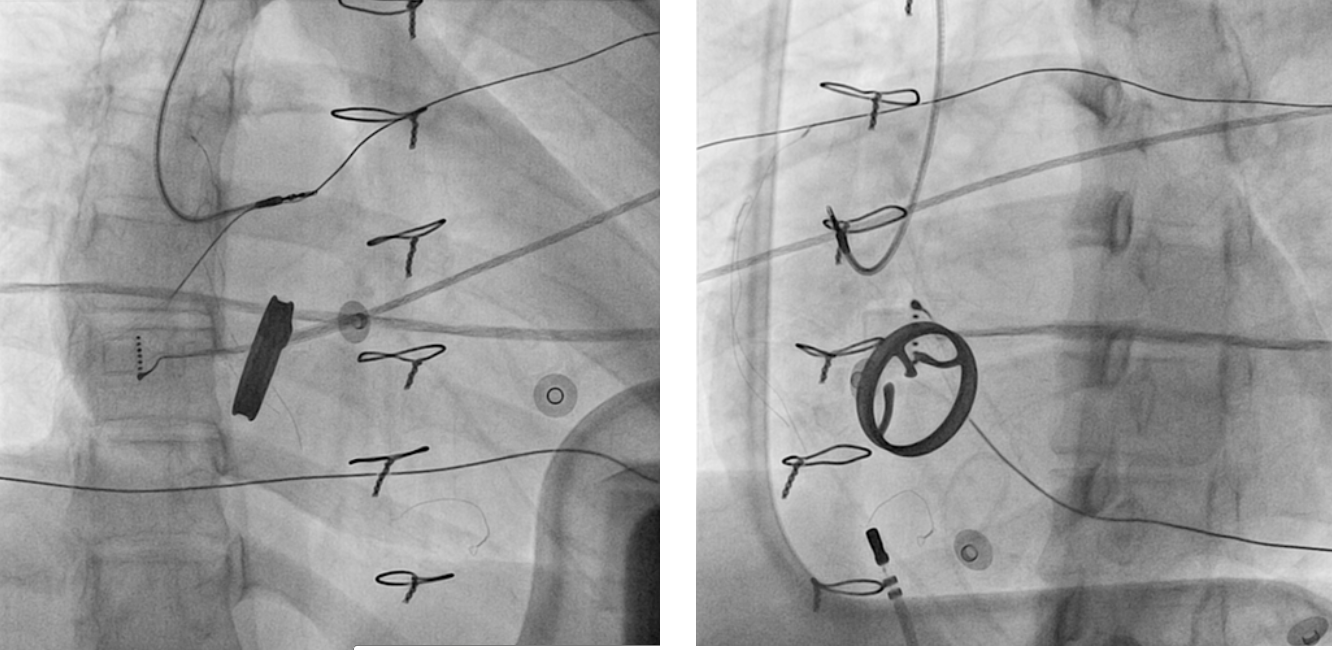

Ablation - Identify isthmus

• Narrow

• Slow conduction

• Easy to ablate

Isthmus

frag_signal.jpg

Ablation - Confirm block

fig3.jpg